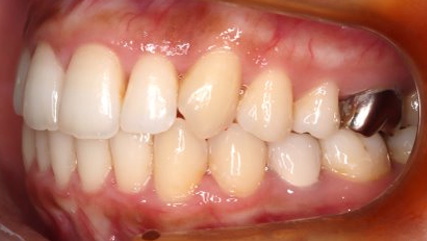

上顎前突といわれ、上顎の前歯が唇側に出ている状態を言います。

前歯が出ることで見た目の問題もありますが、口を閉じることができない、口呼吸をしてしまう、外傷などのリスクがあります。

日本人に叢生の次に多い不正咬合と言われており、自然に治ることはありません。また上の前歯が出ている事だけが気になるかもしれませんが、多くの場合、上顎の奥歯の位置に問題があることが多く、部分矯正でなく根本的な治療をした方がいい場合が殆どです。

口を閉じることができないことで、鼻呼吸でなく口呼吸をしてしまい、結果、成長期の場合顎の骨の成長を邪魔してしまうとも言われております。その他、口呼吸はアトピーなどを含むアレルギー症状の悪化、風邪を含むウイルス性の感染症にかかりやすいなどのリスクも増大してしまいます。

歯並びだけでなく全身への影響も多い為、早期の治療をおすすめ致します。